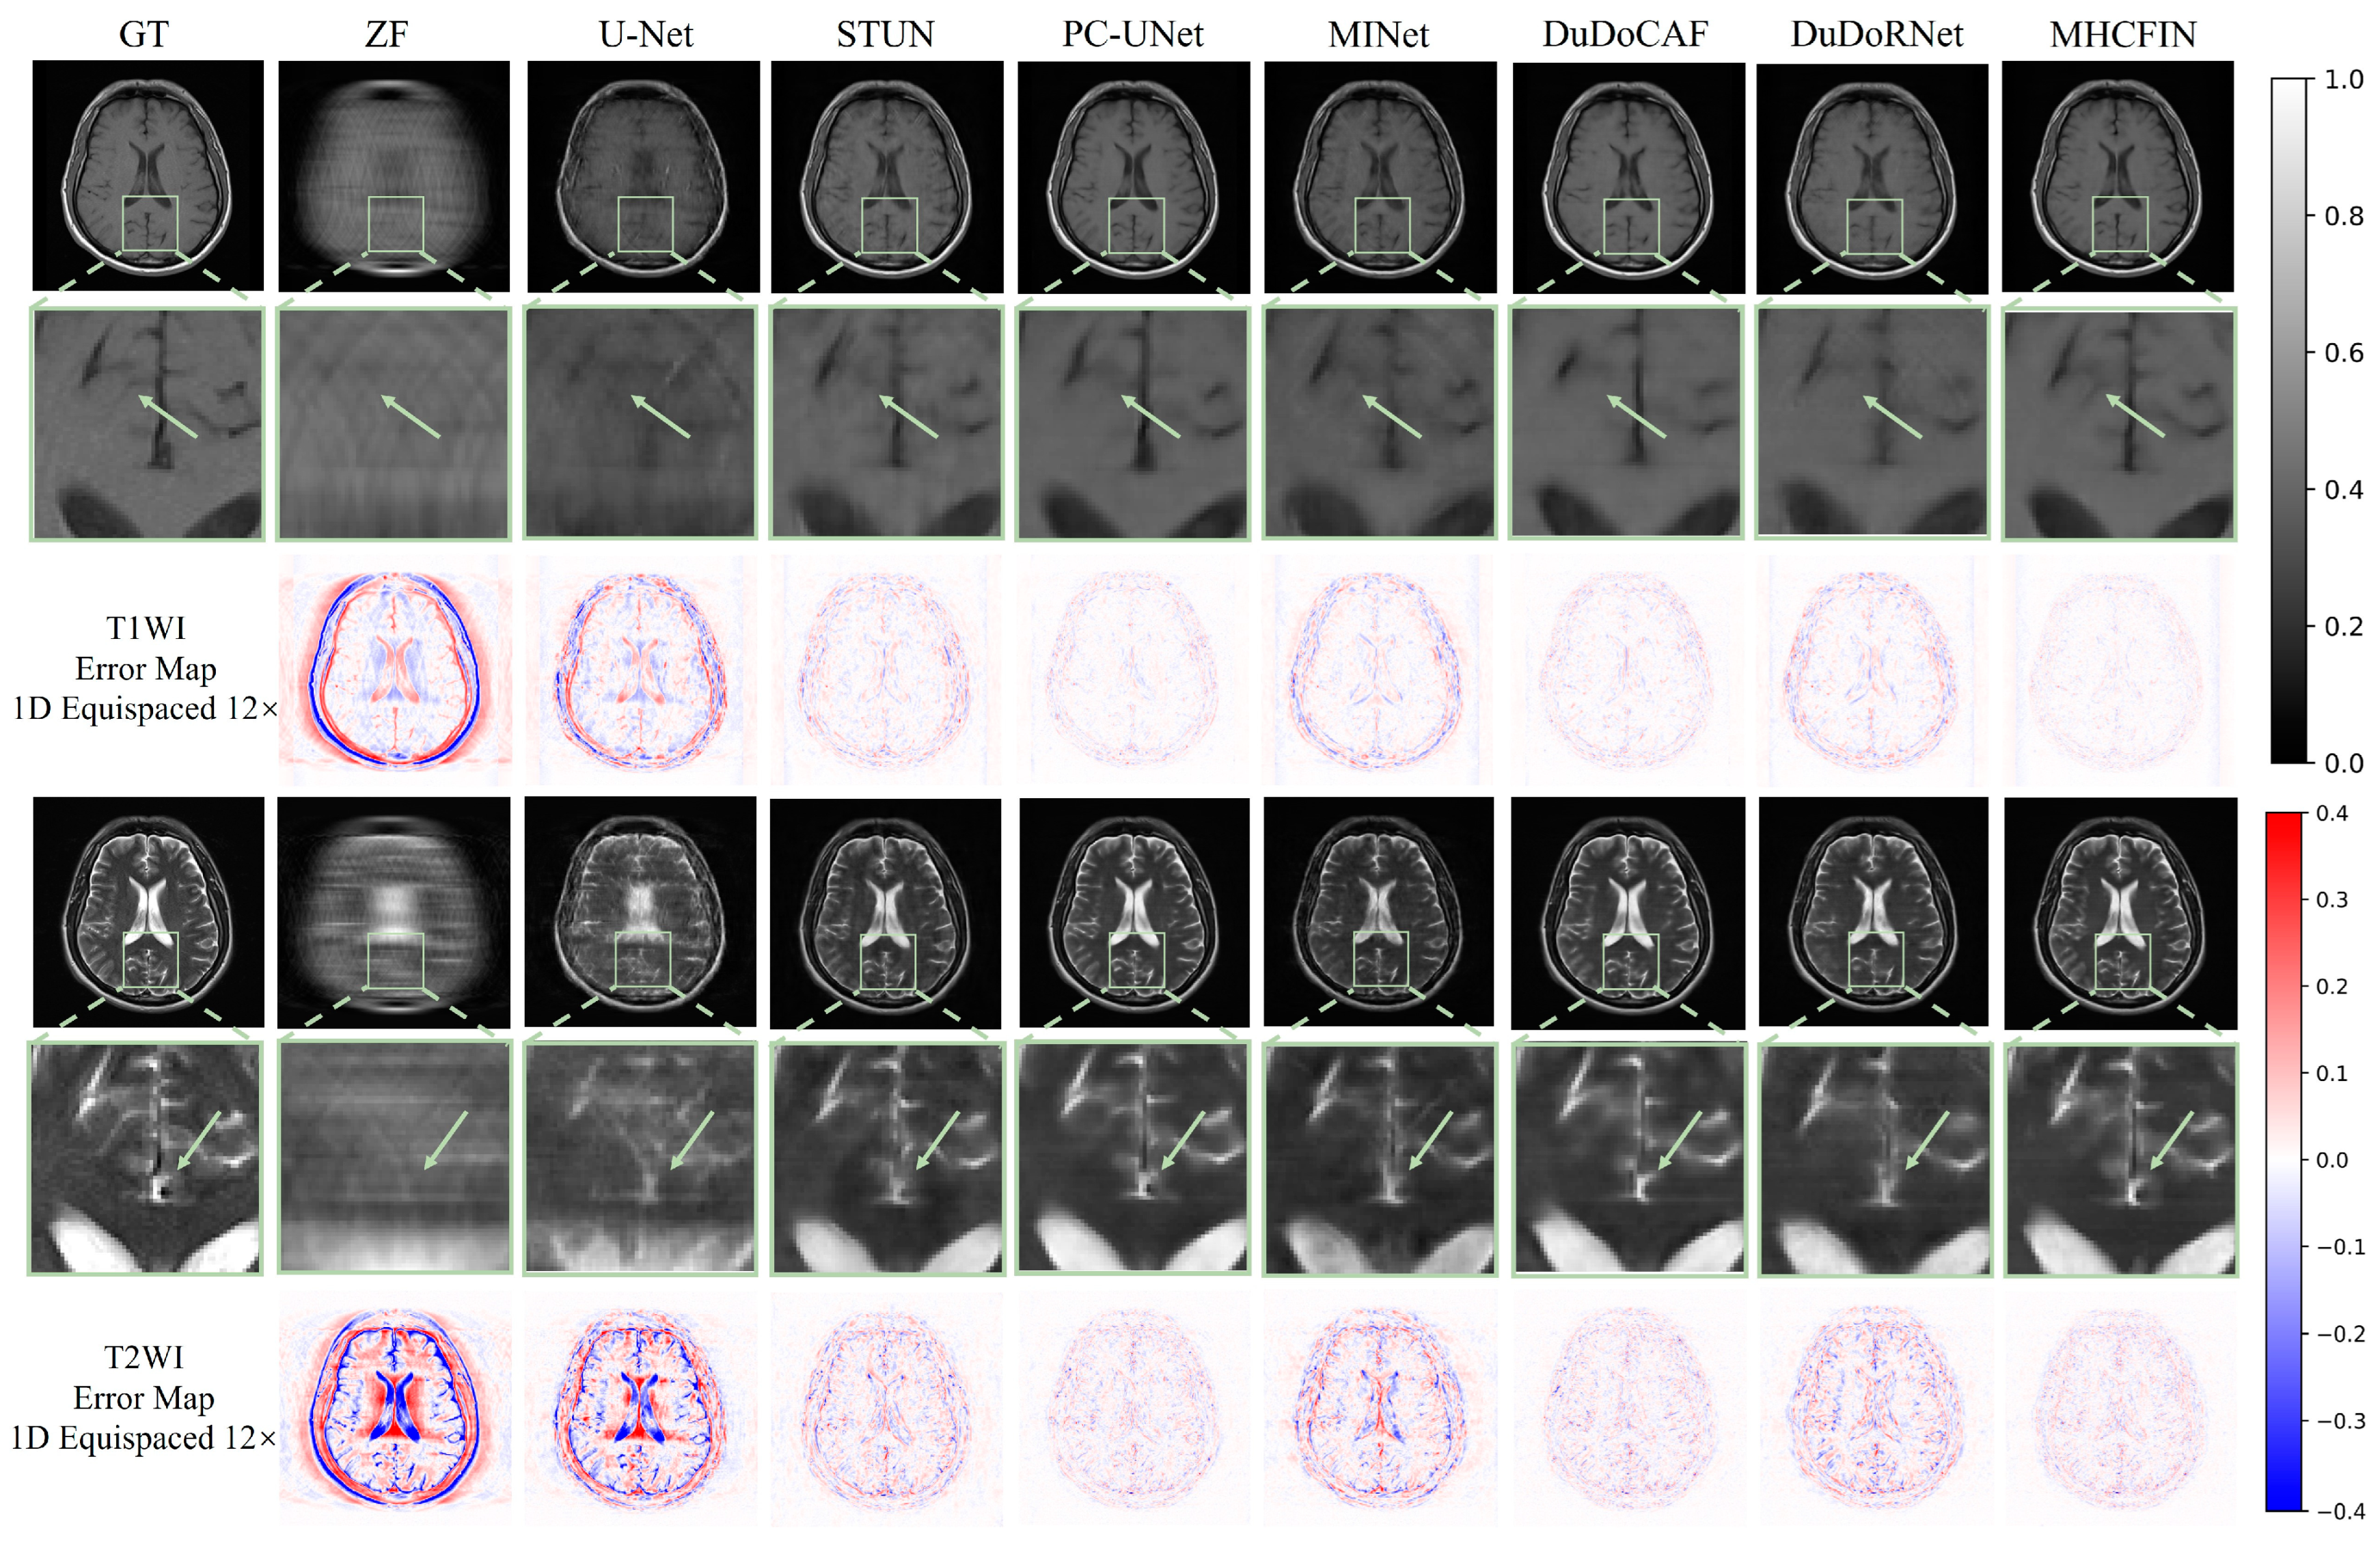

5.2. Qualitative Results

| 1D Random 8× (Mean (Standard)) | ||||||

| ZF | 22.572 (1.057) | 0.620 (0.065) | 0.265 (0.045) | 21.764 (1.054) | 0.673 (0.041) | 0.310 (0.033) |

| U-Net [51] | 33.965 (1.239) | 0.910 (0.024) | 0.072 (0.016) | 30.485 (0.978) | 0.906 (0.031) | 0.113 (0.011) |

| STUN [15] | 34.297 (1.349) | 0.893 (0.028) | 0.069 (0.017) | 30.634 (1.284) | 0.905 (0.037) | 0.112 (0.017) |

| PC-UNet [47] | 37.845 (1.125) | 0.951 (0.016) | 0.046 (0.009) | 34.515 (1.073) | 0.939 (0.024) | 0.080 (0.009) |

| MINet [49] | 33.070 (1.522) | 0.896 (0.028) | 0.081 (0.022) | 28.933 (1.418) | 0.889 (0.044) | 0.137 (0.023) |

| DuDoCAF [27] | 37.443 (0.888) | 0.945 (0.017) | 0.050 (0.008) | 33.675 (0.965) | 0.937 (0.022) | 0.079 (0.008) |

| DuDoRNet [14] | 34.283 (1.229) | 0.908 (0.023) | 0.069 (0.016) | 30.544 (1.009) | 0.907 (0.031) | 0.113 (0.011) |

| MHCFIN | 39.896 (1.073) | 0.964 (0.014) | 0.036 (0.006) | 35.235 (1.049) | 0.948 (0.025) | 0.065 (0.007) |